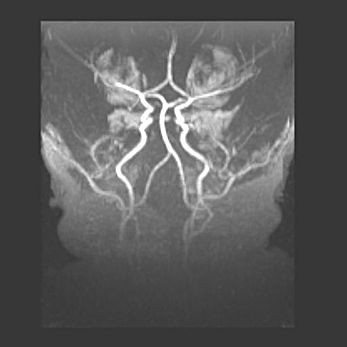

Наружная гидроцефалия с возможной атрофией височных областей.

Возраст: 28 дней

Вес: 3670 г

Пол: мужской

Окружность головы: 38 см

Срок гестации: 40 недель

Гидроцефалия головного мозга у новорожденных – это заболевание, которое характеризуется скоплением избыточного количества спинномозговой жидкости в желудочковой системе головного мозга в результате затруднения её перемещения от места выработки к месту поглощения в кровеносную систему или вследствие нарушения абсорбции. При открытой наружной форме гидроцефалии у новорожденных расширяются и переполняются субарахноидные пространства.

При нормотензивных  формах,  которые,  как  правило,  являются  следствием  перенесенных ишемических  повреждений  паренхимы  мозга,  возможно  сочетание микроцефалии  с нормотензивной гидроцефалией. В основе данных изменений лежит атрофия больших полушарий с преимущественной  локализацией  в  лобно-височных  областях.